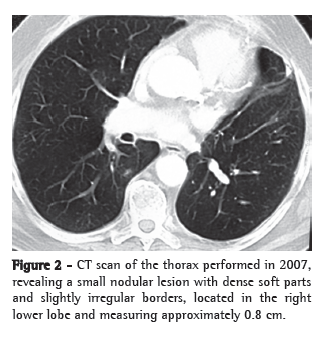

We present the case of a 71-year-old male patient submitted to left upper lobe lobectomy with pericardial resection due to localized invasion and mediastinal lymphadenectomy five years ago (Figure 1). The pathological stage was IIB (T3N0M0). A contralateral pulmonary lesion (0.8 cm) was found in the upper segment of the right lower lobe during a follow-up imaging study (Figure 2). This lesion had not been seen in previous imaging studies. The patient was asymptomatic, had no comorbidities and presented no history of liver disease. He was a former smoker (30

pack-years) who had not smoked for 20 years and described himself as a nonalcoholic. Physical examination at admission revealed no particularities, except for a scar from a left posterolateral thoracotomy.